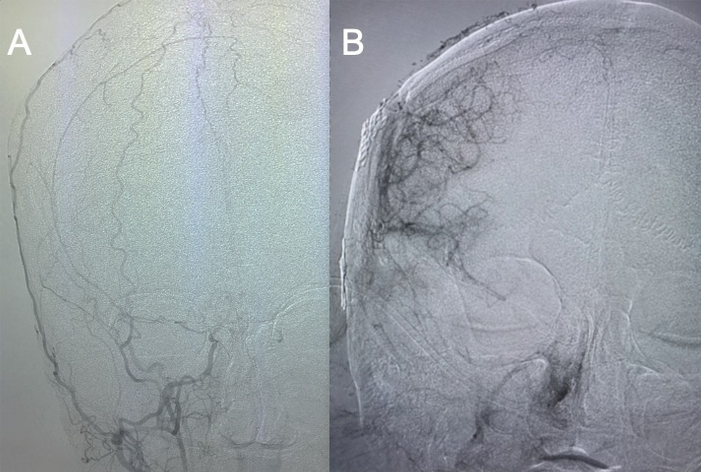

Figure 4: A) Anterior or front view of the right external carotid artery supplying the skin and tissues of the head. B) One year after right EDAS surgery, an angiogram of the right external carotid artery now shows robust vessels supplying the right side of the brain.